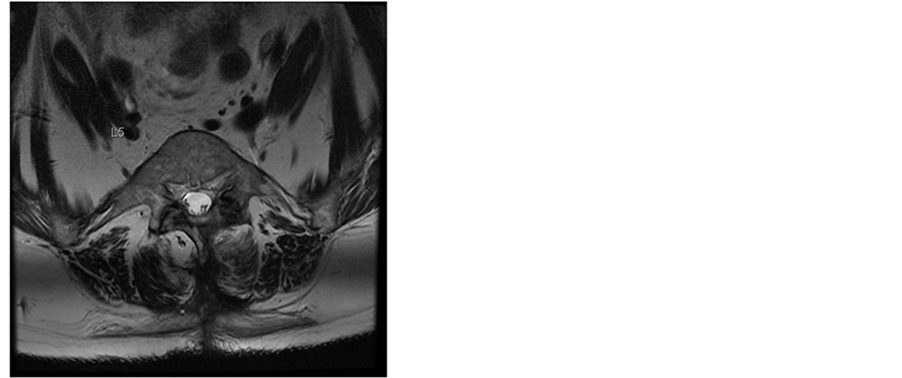

Figure 1. T2-weighted MR images of the lumbar spine 4 days after surgery. Sagittal and axial MR images at L4/5 level demonstrate an acute multisegmental epidural bleeding between L2/3 to L4/5 levels with almost complete obliteration of the spinal canal and severe compression of the dural sac.

Additionally the patient had various comorbidities in her medical records. The acetylsalicylic acid medication, prescribed from her cardiologist because of a coronary heart disease, was discontinued following our routine protocol 7 days before the surgery was scheduled. The operation itself was uneventful. The patient received general anesthesia with systemic opioid analgesics. An interlaminar access was performed at level L2/3, L3/4 and L4/5, the rezessal nerves were released by removing parts of the ligamentum flavum and the internal surface of the hemi-laminae. Perfect local haemostasis was performed as usual, and no Redon drain was inserted therefore. Due to early mobilization and apart from age no additional risk factors, she got no thrombosis prophylaxis according the 2009 guidelines of the Association of the Scientific Societies in Germany [6] . In the first day the postoperative course was uneventful. The analgesic regime was prescribed according to our local routine, containing opioids, 4 g paracetamol and up to 4 g metamizol in 4 single doses per day and the patient was not anticoagulated to prevent thromboembolic issues. Our patient recovered quickly and the analgesics could be reduced, leaving only metamizol and low dose opioids. The patient was already fully mobilized. On day 3 the local pain increased again and at the same time it became increasingly radicular. Due to calf pain she received 40 mg enoxaparine as a single dose that was stopped thereafter as soon as a deep venous thrombosis was ruled out via compression ultrasound. On the same day we performed an MRI of the spine and discovered a big epidural hemorrhage on L2/3 to L4/5 with compression of the dural sac (Figure 1).